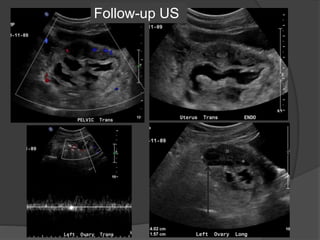

Follow-up US

Case 2: 12 year old female with abdominal pain

Dilated fallopian tube with thickened and enhancing tubal wall

Right

ovary

Complex

tubular

mass

Normal left ovaryNormal left ovary flow

Diagnosis: Torsion of the left Fallopian tube

Dilated tube with thickened, echogenic walls

and absence of vascular flow in the tube

Isolated torsion of the fallopian

tube

 Rare cause of lower quadrant pain primarily affecting

adolescents and ovulating women. Risk factors:PID,

tubal ligation, neoplasm, adhesions, gravid uterus and

trauma.

 Complications include fallopian tube necrosis, an

increased risk for superinfection and peritonitis. Local

necrosis can also result in irreversible damage to the

ipsilateral ovary.

 Treatment options include surgical detorsion,

salpingotomy, and salpingectomy depending on the stage

of intervention and presence of complications.

Companion Case : 32 F with pelvic pain and

fever

Left ovaryLeft adnexa

Right ovary Right adnexa Bilateral adnexa

Dx: Bilateral

pyosalpinges

Increased

flow in the

thickened

and dilated

fallopian

tubes unlike

torsion